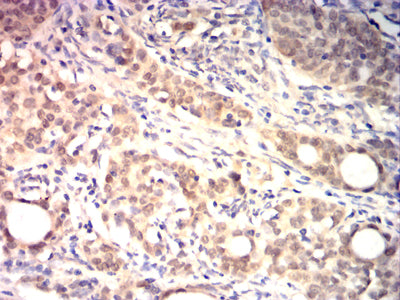

Immunohistochemical analysis of paraffin-embedded human breast cancer tissues using HSP70 mouse mAb with DAB staining.